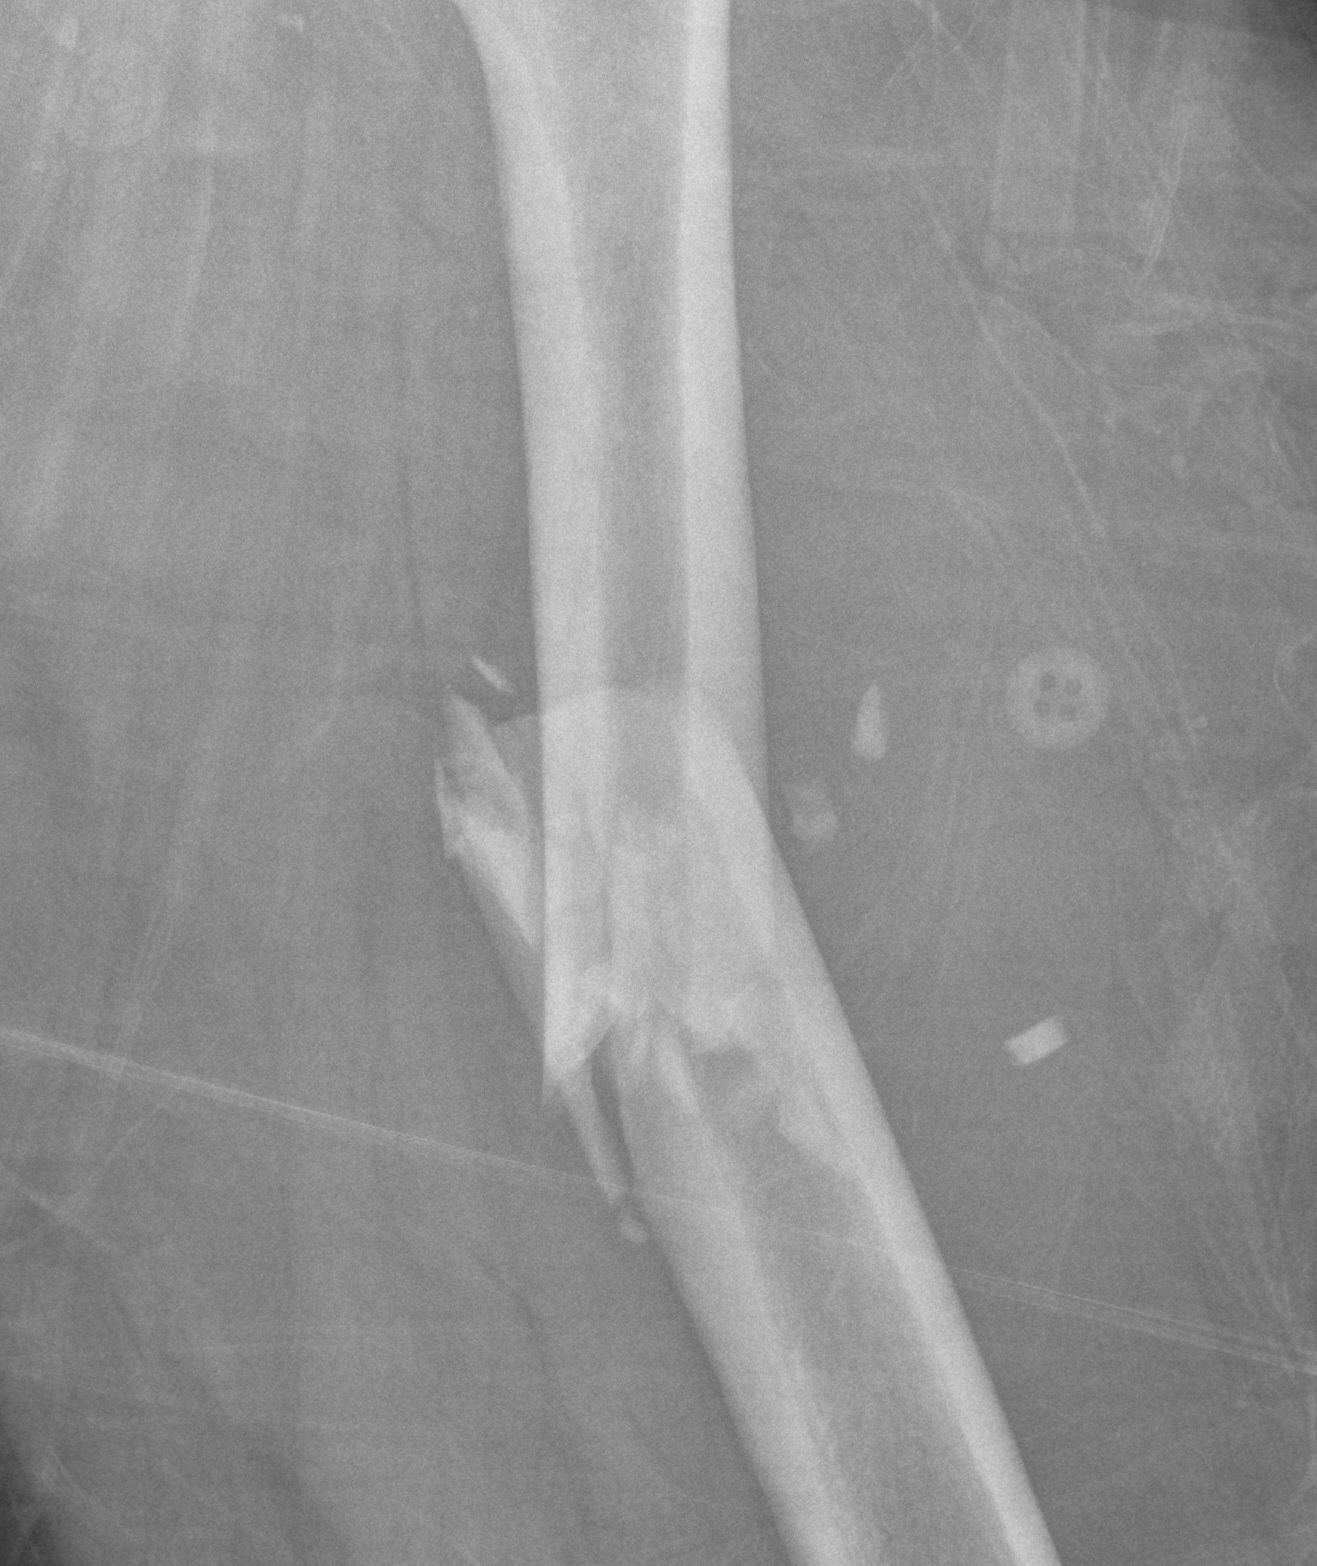

Winquist Classification

Type 1

- minimal or no comminution

Type 2

- < 50% comminution

Type 3

- 50 - 100% comminution

- inherently unstable

- needs distal locking

Type 4

- segmental comminution

- no contact or inherent stability